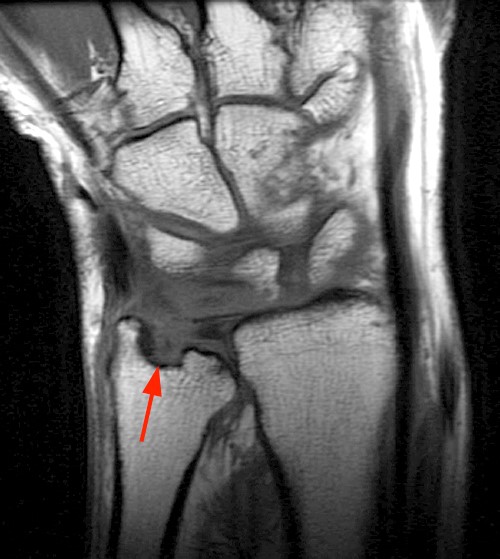

The constellation of findings that includes synovitis in several compartments of the wrist, an erosion in the distal ulna, tenosynovitis in multiple dorsal extensor tendon compartments, and radial and ulnar flexor bursitis are consistent with rheumatoid arthritis.

| Erosion of the distal ulna |